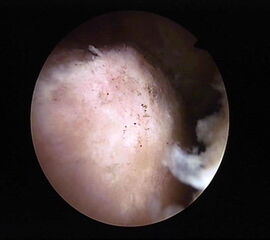

Abbildung 5-7, Video 2

Zunächst wird die Bursektomie (Abb. 5: gerötete Bursa subachillea; C=Calcaneus, B=Bursa, AS=Achillessehne) mit der Radiofrequenzsonde durchgeführt und die Haglundexostose dargestellt. Alternativ kann die Bursektomie mit einem Shaver durchgeführt werden. Hierbei sollte der Ansatz der Achillessehne kaudal einsehbar sein (Abb. 6: C=Calcaneus, AS=Achillessehne) und unbedingt die gesamte mediolaterale Ausdehnung der posterioren Calcaneusfläche erfasst werden (Abb. 7). Häufig liegen Anteile der Exostose weit medial und/oder lateral und werden übersehen.